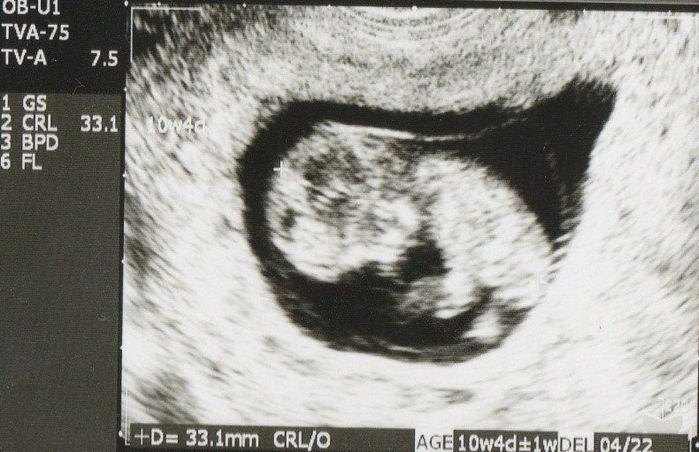

妊娠10週目のエコー写真

胎嚢のなかにすでに人間らしい形に成長している赤ちゃんを発見! 左側に頭、右下のほうが脚のようです。未発達ですが、目や脳と、うっすら白く背骨らしきものが見えます。二度目の生命誕生は、一度目とまた違った感動がありました。

上の画像の拡大です。人間らしい頭と胴体に別れ手足も写っています。ですが、大きさにしてみるとまだまだ33mm。長女は、「あかちゃん?ここ?」と私のおなかとこのエコー写真を、じーっと不思議そうに見ていたのを覚えています。